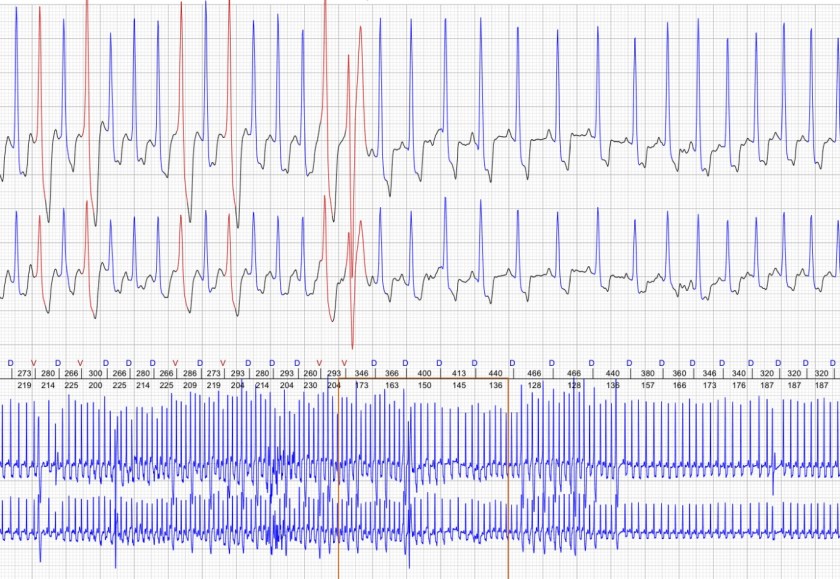

Diagnostyka Kardiologiczna Zwierząt Domowych